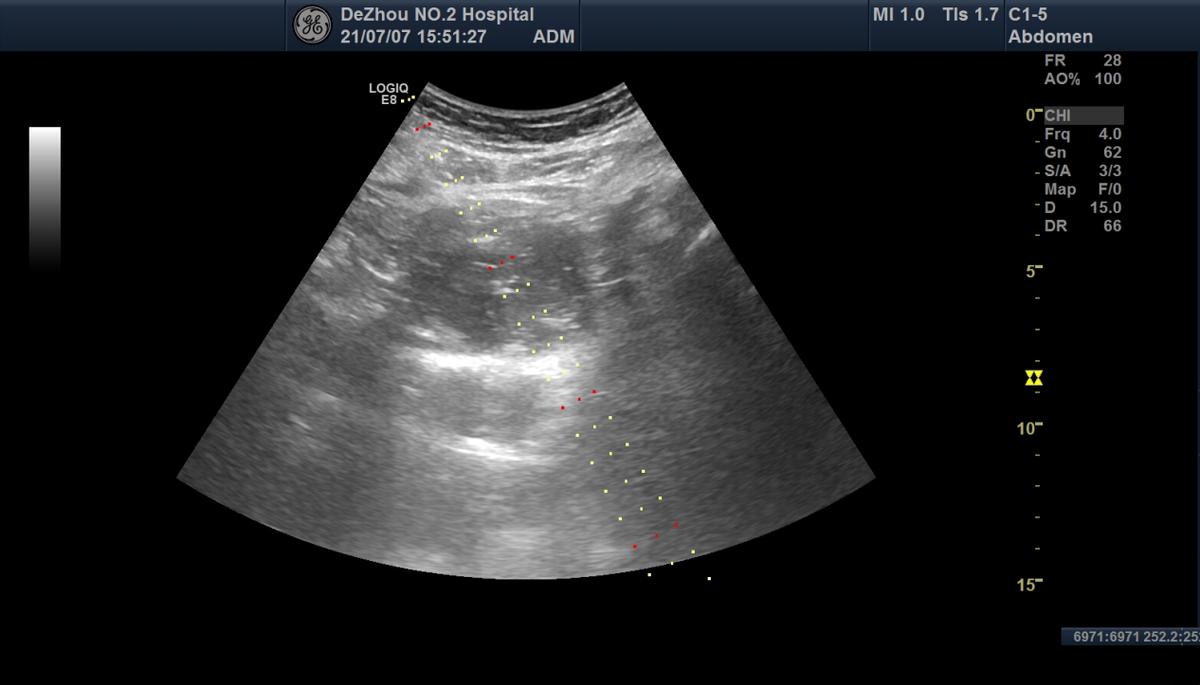

超声确定穿刺路径

超声检查发现:子宫大小形态及内部回声正常,右侧附件区可见6.9×5.2cm大小的囊性肿物,与右侧卵巢相连,呈圆形,壁厚,表面光滑,内部透声差,可见细密的点状回声,囊内无分隔,后方回声有增强,肿物可随体位移动至膀胱上方。超声提示:右侧卵巢囊性肿物 考虑子宫内膜异位囊肿(巧克力囊肿)。

患者仰卧位,彩超扫描下腹部确定穿刺路径,消毒铺巾,安装穿刺引导架,局部麻醉,采用18G PTC穿刺针,经皮肤进入囊肿内,抽出巧克力色粘稠囊液174ml,用0.9%的生理盐水200ml分4次冲洗囊腔至冲洗液清亮,无水乙醇硬化剂50ml注入囊腔内保留(反复抽吸)10分钟抽出。拔针敷贴,治疗结束。